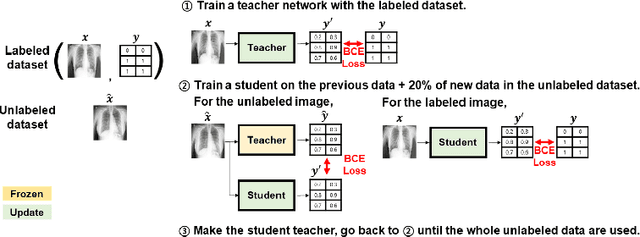

Abstract:Although deep learning-based computer-aided diagnosis systems have recently achieved expert-level performance, developing a robust deep learning model requires large, high-quality data with manual annotation, which is expensive to obtain. This situation poses the problem that the chest x-rays collected annually in hospitals cannot be used due to the lack of manual labeling by experts, especially in deprived areas. To address this, here we present a novel deep learning framework that uses knowledge distillation through self-supervised learning and self-training, which shows that the performance of the original model trained with a small number of labels can be gradually improved with more unlabeled data. Experimental results show that the proposed framework maintains impressive robustness against a real-world environment and has general applicability to several diagnostic tasks such as tuberculosis, pneumothorax, and COVID-19. Notably, we demonstrated that our model performs even better than those trained with the same amount of labeled data. The proposed framework has a great potential for medical imaging, where plenty of data is accumulated every year, but ground truth annotations are expensive to obtain.